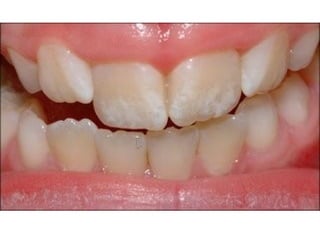

Ανωμαλίες διάπλασης της αδαμαντίνης

 Παθογεvνετικά διακρίνονται δύο μορφές

υποπλασία – μια ποσοτική ανωμαλία

της αδαμαντίνης, εντοπισμένη ή

γενικευμένη μείωση του πάχους που

οφείλεται σε διαταραχές στην εκκριτική

φάση

 Υπενασβεστίωση – διαταραχές κατά το

στάδιο της ενασβεστίωσης, έτσι τμήματα

της αδαμαντίνης αποσπώνται γρήγορα

Υπενασβεστίωση γομφίων και τομέων

 Επιπολασμός 4 - 25% ανάλογα με τον

πληθυσμό που εξετάζεται

 Ο αριθμός των δοντιών ποικίλει από ένα

έως τέσσερα

 Ο βαθμός προσβολής ποικίλει από ελαφρώς

έως βαριά